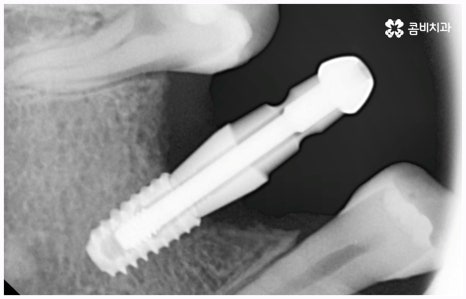

비용이나 시간적인 부담이 만만치 않기 때문에 임플란트를 보다 오랜 기간 동안 건강하게 사용하려면 어떻게 해야 하는지 궁금해 하시는 분들이 많이 있으실 거예요. 임플란트 식립 성공률 및 지속률에 가장 크게 영향을 주는 것은 환자분들의 잇몸뼈 건강 상태 및 술자의 숙련도라고 할 수 있는데요. 예를 들어 구강 질환을 원인으로 한 병증이 심각하거나 치아를 상실한지 오랜 시간이 지나 잇몸뼈의 흡수가 많이 일어났기 때문에 높이와 밀도 등이 식립을 진행하기에 충분하지 않다면 뼈이식을 선행하여 기반부터 튼튼하게 보충해 줄 필요가 있어요. 또한 노화로 인해 상악동이 내려왔다면 상악동 거상술을 통해 공간을 확보해 주어야 하는데 이렇게 고난도 수술의 경우 다양한 임상 경험을 통해 풍부한 노하우와 뛰어난 기술력을 가지고 있는 의료진과 함께 하는 것이 무엇보다 중요하다고 할 수 있습니다.

이때 심장 질환이나 당뇨, 고혈압 등 전신 질환을 앓고 계신 분들 중에 감염에 취약하고 약물에 의한 혹시 모를 합병증이 걱정되어 임플란트 식립을 망설이시는 분들이 있을 수 있는데, 검진 및 상담을 철저하게 진행한 후에 주치의와 협진하여 상용약 의 복용 스케줄을 미리 조절해 주고 섬세한 치료 계획과 시술 과정을 통해 환자분들의 상황에 딱 맞는 임플란트 종류 를 무리하지 않게 식립하게 되면 잇몸 조직 손상을 최소화하여 환자분들의 부담을 줄일 수 있을 것이니 막연한 두려움으로 인해 치아 상실 후 시간을 지체하시기 보다는 될 수 있는대로 빨리 내원하셔서 필요한 치료를 받으시는 것이 좋을 거예요.